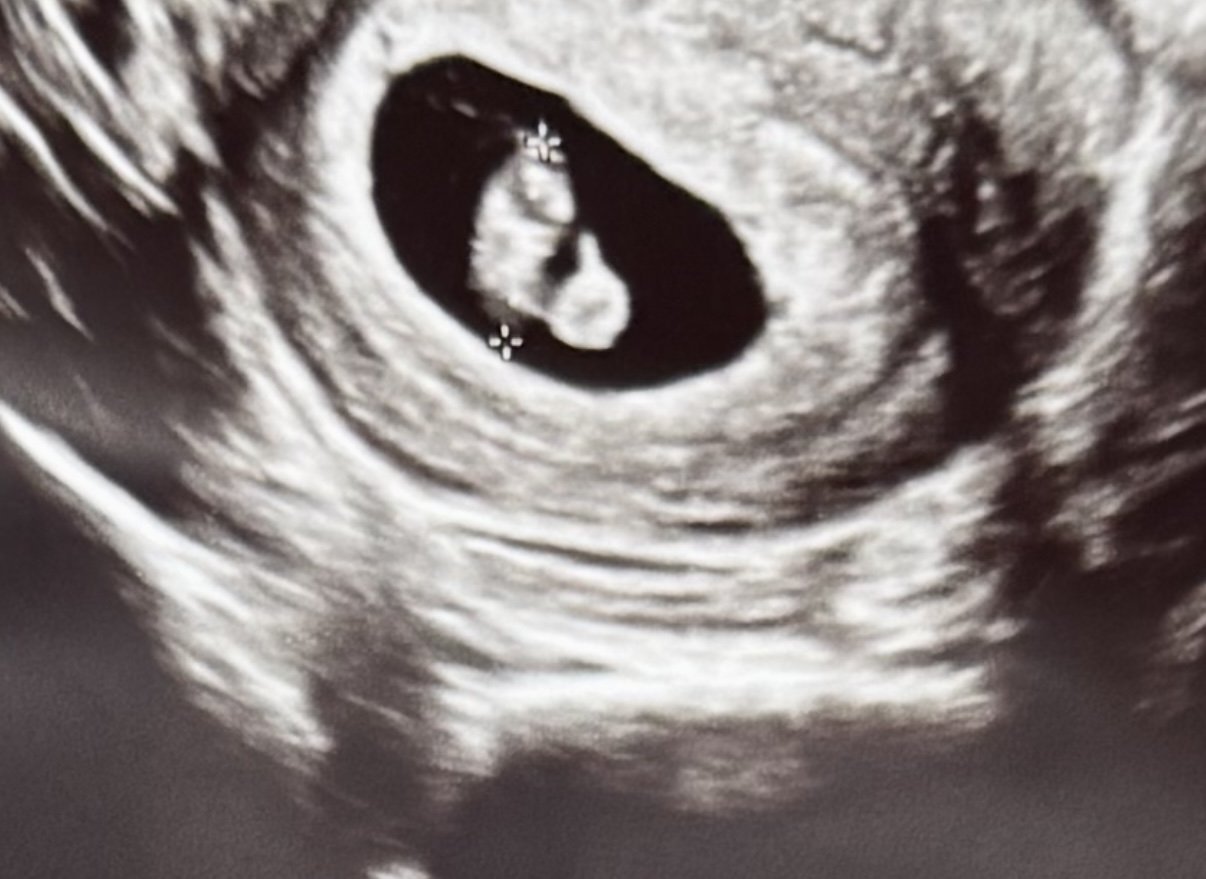

Здравейте. 7 седмица и 5 ден съм. Може ли да ми кажете от опита ви от ваши ехографи на смимката какво е кръгчето и телцето? Понеже не ми поясни доктора.

Не съм медицинско лице, но на един от първите прегледи доктора каза, че в началото се формира плоден сак с ембрион и жълто мехурче, което изчезва в един момент.

Това трябва да са ембрион и жълто тяло.